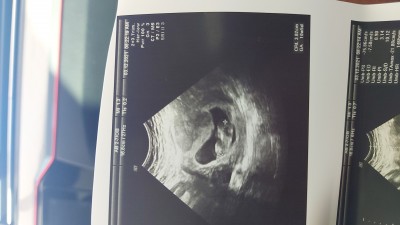

Cinsiyet tahmino yapabilirmsns

Gebelik haftası 10+6

Kapatılma nedeni: Cinsiyet tahminlerini sol üst köşeden konu dışı sohbetten sorabilirsiniz

Bu haftada bebeğin cinsel organı oluşmuyor ki. Ben 14 haftaya girecem daha öğrenenedim.